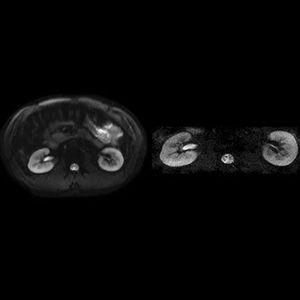

ZOOMit is the first clinical application for parallel transmit technology. Powered by @siemens parallel transmit architecture, TimTX TrueShape, ZOOMit uses dynamic excitation pulses to achieve selective field-of-view (zoomed) imaging, without aliasing artifacts. Imaging is faster, with less susceptibility artifacts and geometric distortions. Zoom into your image to appreciate the smallest details, to improve diagnostic confidence and expand research possibilities. Figure MR Diffusion for renal imaging, better differentiation between cortex and medulla Left: conventional DWI with 2.1 mm x 2.1 mm. Right: ZOOMit DWI with 1.4 mm x 1.4 mm.